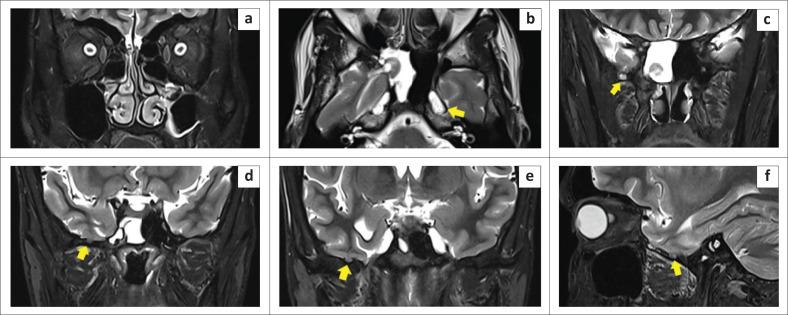

Intrasphenoidal encephalocoeles are acquired or congenital herniations of meninges and brain parenchyma through a structural sphenoid bone defect. Acquired causes are most common, either iatrogenic, post-traumatic, or spontaneous. However, defects in the lateral wall of the sphenoid sinus are uncommon and cephalocoeles through them relatively underexplored in current literature, warranting dedicated attention to unravel their complexities. Congenital causes such as persistence of Sternberg's canal, which can lead to lateral cephalocoeles, is a rare entity, seen in two of the presented cases, based on the location of the defect with respect to the line connecting the foramen rotundum and the vidian canal (VR line). Three cases of intrasphenoidal cephalocoeles are presented; two patients presented with watery nasal discharge without prior trauma or surgery and the third case was incidentally detected in an elderly patient with intraparenchymal haemorrhage. Imaging with CT cisternography and brain MR were performed to ascertain the exact location of the leak and confirm the presence of herniated brain tissue via the defects. Patients were evaluated by otolaryngology for transnasal endoscopic repair, which was deemed unfeasible, and referred to neurosurgery for transcranial duroplasty.

蝶窦内脑膨出是指脑膜和脑实质通过蝶骨结构缺损形成的后天性或先天性疝出。后天性病因最为常见,包括医源性、创伤后或自发性病因。然而,蝶窦外侧壁缺损并不常见,目前文献中对通过这些缺损形成的脑膨出研究相对较少,因此需要专门关注以揭示其复杂性。先天性病因如施特恩贝格管持续存在可导致外侧脑膨出,这是一种罕见情况,在所呈现的两例病例中可见,其依据缺损相对于连接圆孔和翼管的线(VR线)的位置而定。本文呈现了三例蝶窦内脑膨出病例;两例患者表现为水样鼻溢液,无既往创伤或手术史,第三例在一名老年脑实质内出血患者中偶然发现。进行了CT脑池造影和脑部磁共振成像以确定漏口的确切位置,并通过缺损确认疝出脑组织的存在。患者接受了耳鼻喉科评估以进行经鼻内镜修复,但认为不可行,随后转诊至神经外科进行经颅硬脑膜成形术。

这些病例为蝶窦内外侧脑膨出的病因提供了关键见解,提供了一个基于骨缺损位置对脑脊液(CSF)漏进行分类的实用系统。这三例说明性病例以及对先进成像方式的强调完善了对其病因、临床表现和治疗的认识,这对于准确诊断和针对性治疗这些罕见异常具有直接临床意义。